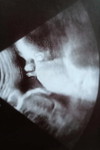

Hello po mga super mommy.. Tanong ko lng po kung natural po ba sa pregnant ung hirap po sa pag pupu?parang bloated po tpos inaabot cya ng 3days or 4days bago mka pupu..worried po kse ako sa partner ko she's at 17weeks pregnant po and our 1st baby...thankyou po and God bless you all po mga super mommy??☝️